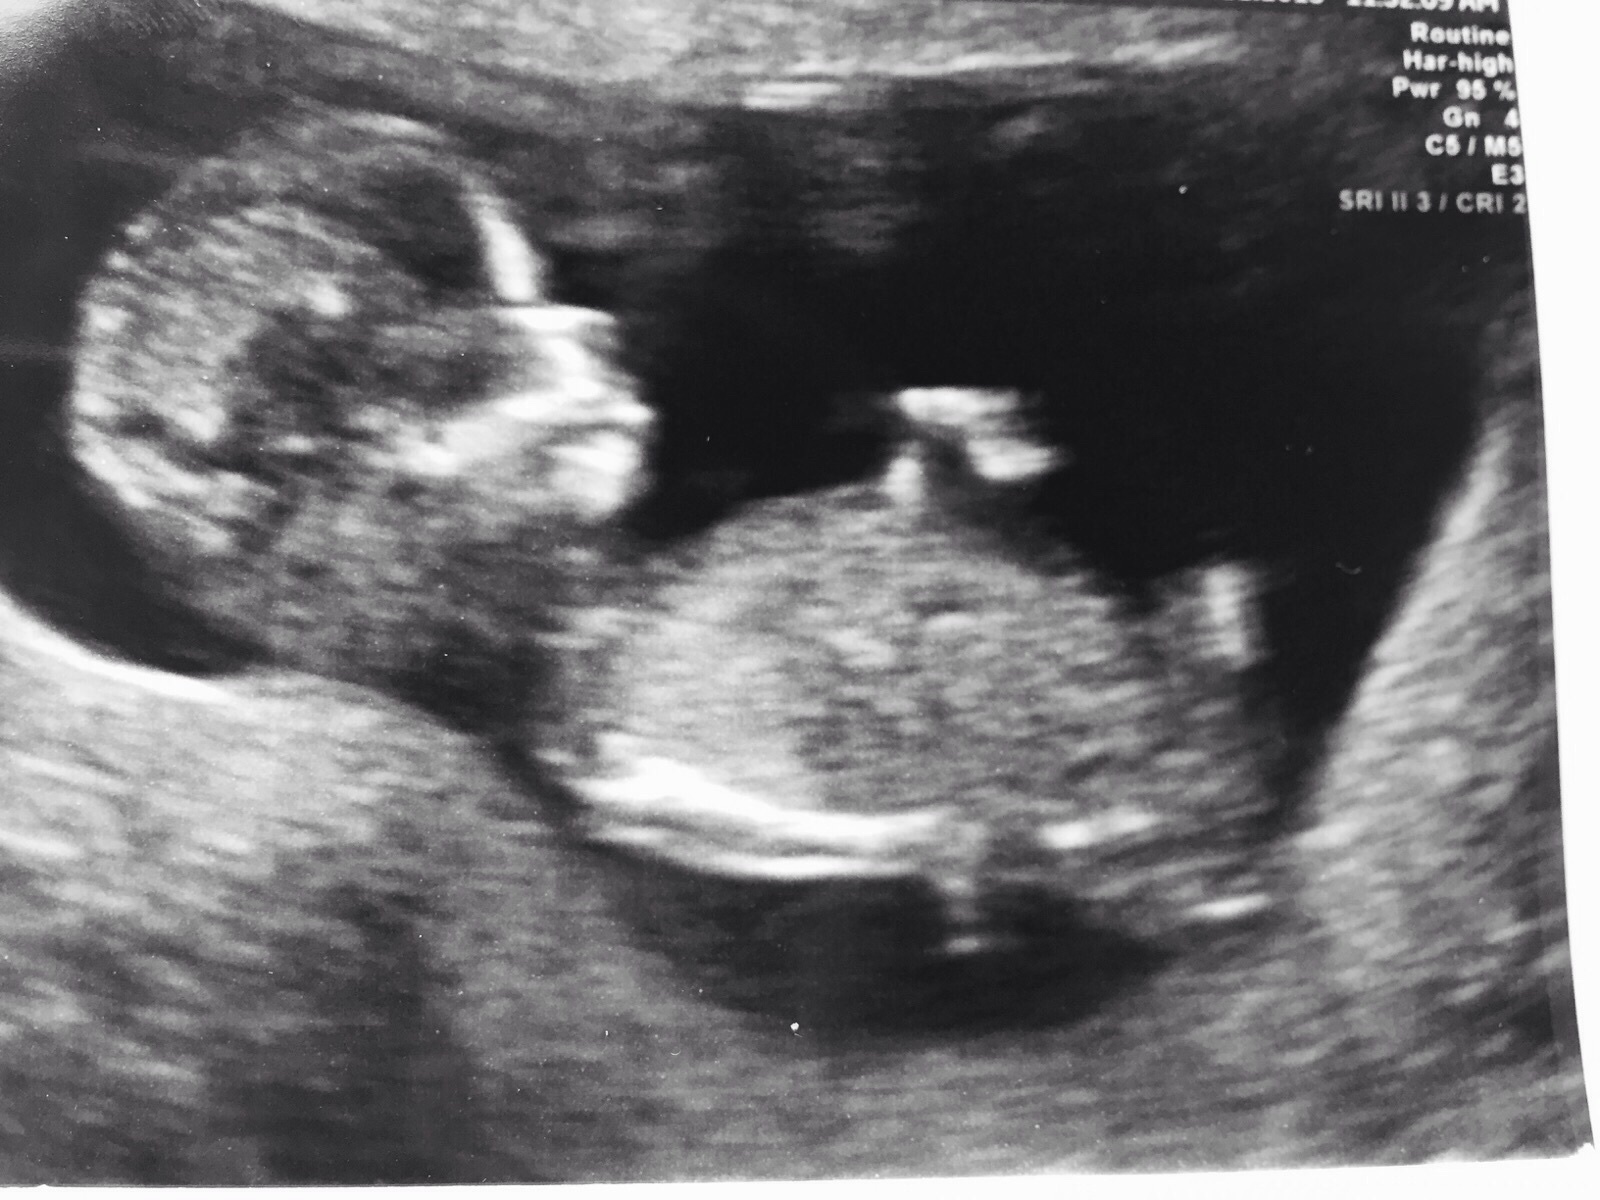

Hiya girls - I'm posting on behalf of a friend. They weren't swaying and happy with either gender, but would like to know what you guys this this little one may be.....boy or girl?

I'm not sure if that is a boy nub or a cord... Does she have more pics?

I'll go for a boy guess then :)